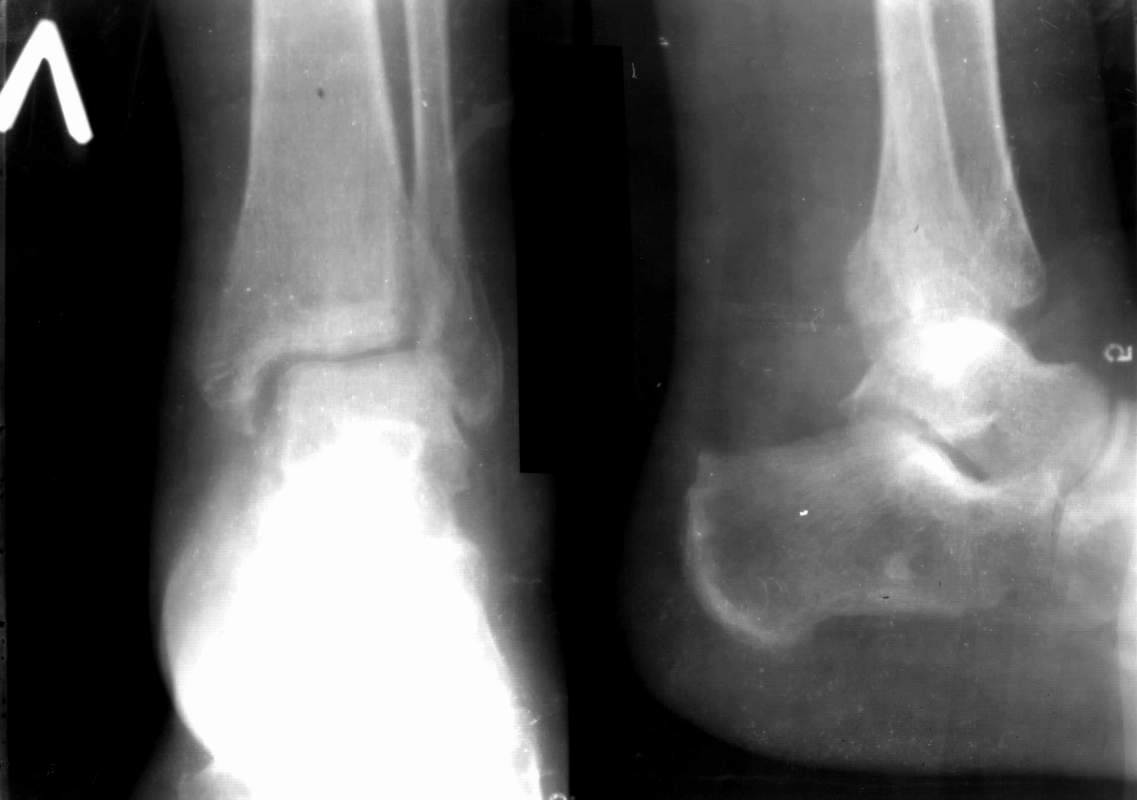

Sergey Melashenko 19 Август 2006, 12:43

Ув. коллеги.

После проведенной дискуссии пришел к выводу, что трансартикулярная диафиксация не совсем приемлима с учетом современных методик остеосинтеза. Кроме того, вычитал, что хрящ разрушается на расстоянии до 0,5 см от места проведения спицы.

Пока я был в интернатуре, предпочитали осуществлять стабильный остеосинтез с ранней функцией. См. приложения и полнотекстный вариант

статьи.